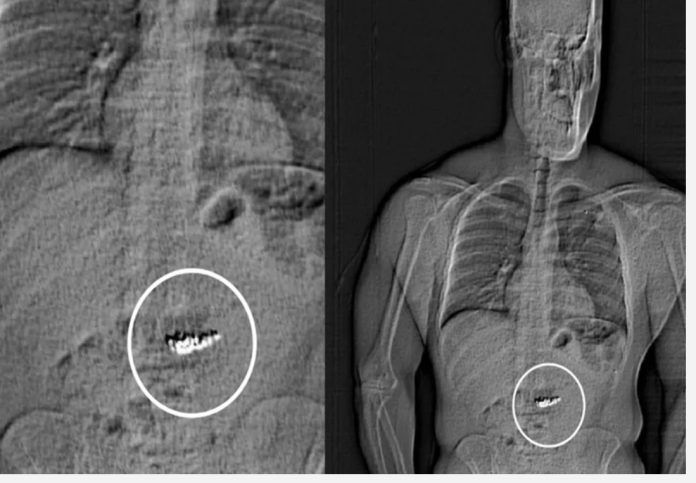

وخلال مطاردة قصيرة، تمكنت الشرطة الأميركية من إلقاء القبض على المتهم، الذي رفض الامتثال لأوامرها. وبعد نقله إلى مركز الاحتجاز وإخضاعه للفحص الطبي، اكتشف المسؤولون وجود الأقراط داخل معدته.